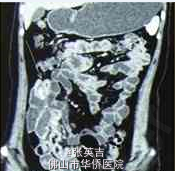

患者生命体征平稳,营养良好。心肺(-),腹软,脐右深压痛,无反跳痛、肌紧张,肠鸣音亢进,未及包块。 妇科B超检查提示:子宫双附件未见明显异常。 全消化道造影提示:远段回肠占位病变(图1)。 腹部盆腔增强CT及小肠重建检查提示:在右下腹,肠腔内有占位,考虑息肉致肠套叠的可能性大,局部系膜血管影增多,周围有大量渗出影及小淋巴结(图2、3)。